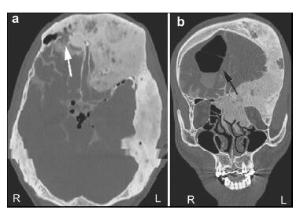

20161117200932  Figure 1 (a, b) A computed tomography (CT) scan demonstrating the expansion of multiple skull bones. The involved bones present with various appearances of mixed radio-dense/radio-lucent lesions, which can be described as “ground-glass”, “lytic”, and “cystic”. Left: Axial CT cisternography demonstrates a fistula at the posterior wall of the right frontal sinus (white arrow). The density of both frontal involved bones is slightly lower than for other skull bones. Right: A coronal CT scan demonstrates pneumocephalus in the right frontal lobe (black arrow).